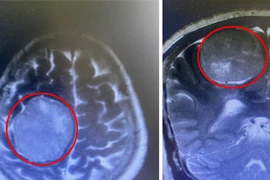

U não tái phát thần tốc, bệnh nhân vượt cửa tử qua ca phẫu thuật căng não

Bệnh nhân người Campuchia thoát khỏi tử thần nhờ ca mổ đặc biệt, khống chế khối u lớn đe dọa mạng sống trong vùng tiểu não nhạy cảm.